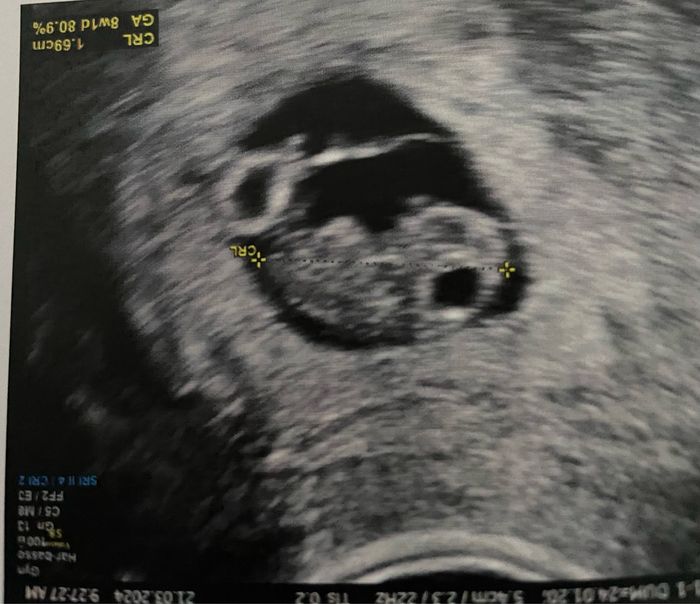

Ah, questa l' immagine di oggi

Eccomi. Sono già a casa, ecografia fatta in anticipo. Sarà durato tutto 5 minuti. Sta bene, è circa 1 cm e mezzo, il cuore batte. È in linea con la datazione. Non ho sentito il cuore purtroppo, speravo proprio. Mi hanno detto che con loro (reparto PMA ospedale) ho finito, di aggiornarli se voglio ogni tanto, ma di proseguire con il mio ginecologo curante. Mi hanno confermato che devo dire come ultima mestruazione il 24/1 (anche se la vera è stata il 23/1). Ho aggiornato l app che ho per la datazione ma continuerò a viaggiare x un po' su entrambe le date finché non mi abituo. Più che altro xké l altra era molto significativa x me e sono un po' dispiaciuta di cambiarla (so che è una data che non vuol dire nulla!). Praticamente loro non mi hanno detto nulla se non di continuare la terapia. I 3 progeffik al giorno fino all inizio della 12esima settimana. Cardioaspirina invece vado avanti. Null'altro. Adesso avrò gli appuntamenti miei l'11 e il 19 aprile, sto decidendo se prendere un appuntamento dal mio ginecologo ancora il 5 aprile x coprire il buco di 3 settimane da adesso. Sono 92 euro buttati ma essendo ancora un periodo delicato non so se voglio restare con l'incognita.

Nooo sembra un orsetto gommoso come dice Sara!!! Si vedono braccine e gambette giΓ

Uhhhh come si vede bene! Effettivamente il mio padre un bamboccio πŸ˜‚πŸ˜‚πŸ˜‚πŸ˜‚

Che buffo in questa immagine! A me era messo di profilo sembra una piccola larva 🀣

Che bello laura, anche tu un piccolo orsetto gommoso